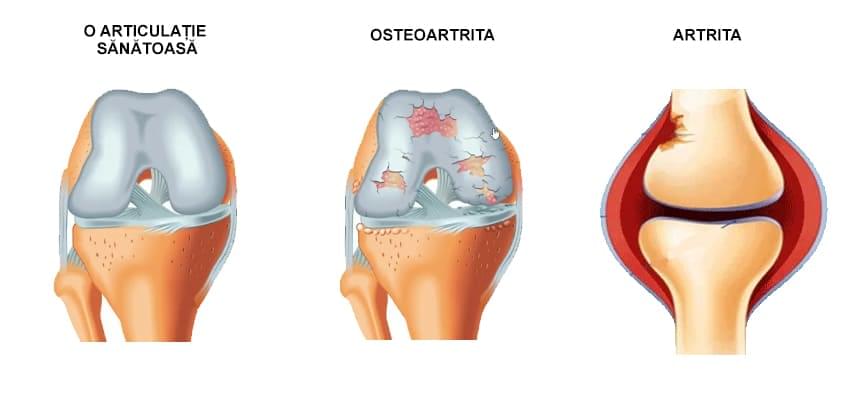

În acest caz, artrita și osteoartrita afectează foarte des persoanele apte de muncă, ceea ce înseamnă că oamenii devin incapabili să muncească - sau trebuie să suporte în mod constant durerea pentru a-și câștiga existența .

Numai în România, conform cifrelor oficiale, există peste 750.000 de persoane cu osteoartrită și aproximativ 200.000 de persoane cu artrită reumatoidă (aproximativ o treime dintre acestea au dizabilități severe).

Prevalența artritei și a osteoartritei este în creștere. Între 2010 și 2020, de exemplu, incidența osteoartritei a crescut cu 48%. Osteoartrita apare la unul din trei pacienți cu vârste cuprinse între 45 și 64 de ani și la 60-70% dintre pacienții cu vârste de peste 65 de ani.

Potrivit OMS, osteoartrita genunchiului este a patra cauză principală de dizabilitate la femei și a opta cauză principală de dizabilitate la bărbați.

Uitați-vă la aceste imagini, puteți vedea că în imaginea din dreapta nu există un spațiu articular, oasele se freacă una de alta, provocând multă durere. Iar acest proces este foarte greu de oprit !

Cât timp credeți că este nevoie pentru ca țesuturile să se degradeze și articulația să se uzeze?".